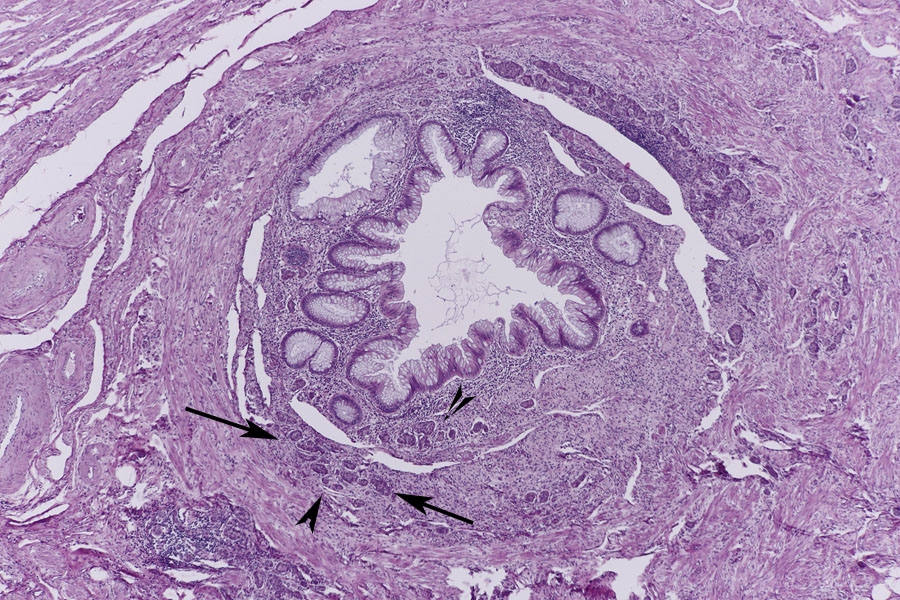

Im erste Blöckchen fand ich vom Aufbau einen typischen Appendix mit Mucosakrypten,

einer Submucosa mit Lymphfollikeln, einer inneren Ring- und einer äußeren Längsmuskelschicht so wie einem Mesenterialansatz. Was mich zuerst etwas irritiert hat war, das sich doch hier weniger Sekundärfollikel finden als ich es von anderen Präparaten gewohnt war. Das mag daran liegen, dass die meisten Appendixpräparate ja eine Appendizitis (Blinddarmentzündung) zeigen. Ronald Schulte hat das in einen tollen Beitrag im letzten Dezember beschrieben.

Ein zweites Präparat zeigt auch wieder den typischen Aufbau des Appendix und wenig gut abgrenzbare Sekundärfollikel.

Anfänglich war ich etwas irritiert durch zottenartige Bildungen der Schleimhaut, so wie eine sehr breite Submucosa. Doch sollten Zotten ja Blut-

und Lymphgefäße, so wie glatte Muskulatur enthalten die ich hier nicht gefunden habe, also sind es keine Zotten sondern nur Ausstülpungen

der Schleimhaut.

Der dritte Block zeigte dann endlich was auf der Schachtel stand, ein Carcinoid

(rein morphologisch).

Es findet sich ein Darmabschnitt mit einer Mucosa die sehr viele Becherzellen enthält,

so wie einer breiten Submucosa. Auch hier sind die Sekundärfollikel nicht sehr ausgeprägt.

In der Submucosa fallen dann Inseln aus Zellen mit hellem Zytopasma auf (Pfeile) die ich

für Carcinoidzellen halte.

Übersicht